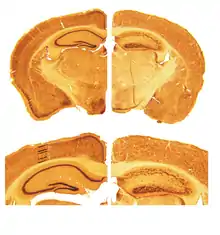

Термін «рилін» походить від англ. to reel — «крутитися», «вертітися», «йти нетвердою ходою». Саме така, «закручена», нерівна хода була помічена у мишей з генетично зумовленою нестачею риліну. Гостра нестача білка призводить до порушення міграції нейронів. Якщо ген, який кодує синтез риліну, виключено повністю (гомозиготний генотип), спостерігається інверсія шарів кори головного мозку. При гетерозиготному генотипі, порушення мозку у мишей менш помітні, але нагадують порушення мозку людини при психотичних розладах[10]. У людини генетично зумовлена відсутність риліну приводить до лісенціфалії, важкої розумової відсталості та епілепсії. Значна нестача риліну у людини спостерігається при шизофренії та біполярному розладі[12], але слід відзначити ймовірну дію медикаментів. Є дані про ймовірні зв'язки поліморфізмів гена RELN з шизофренією[13] та хворобою Альцгеймера[14].

![]() Кортикогенез у дикої миші. Клітини Кахаля-Ретціуса (червоні) виділяють рилін (оранжевий). |

![]() Порушений кортикогенез у миші-мутанта reeler. Рилін відсутній, шари кори інвертовані. |

Миша, названа reeler, була вперше описана в 1951 році британським генетиком Дугласом Скоттом Фальконером[15]. У 1960-ті роки було виявлено, що мозочок у цих мишей набагато менший від норми, до того ж порушена нормальна організація нейрональних шарів[16]. Мутація особливо зацікавила дослідників після того, як було виявлено, що шари нейронів у мишей вистроюються «навпаки»: молодші нейрони були нездатні подолати шари клітин, що вже «осіли» на своєму рівні[17].

Другий процес в розвитку мозку, що залежить від наявності риліна — кортикогенез, зокрема, розщеплювання передпластинки (англ. preplate) на маргінальну зону і субпластинку і заселення простору між ними — кортикальної пластинки — п'ятьма горизонтальними шарами нейронів в «зворотному» порядку. Зворотний порядок побудови шарів кортикальної пластинки, при якому молодші нейробласти долають ряди клітин, що вже прижилися, і вибудовують свій шар вище, відрізняє мозок ссавців від еволюційно стародавнішого мозку зауропсидів, в якому шари будуються «зовні всередину». За відсутності риліну, кортикальні шари миші-мутанта reeler також будуються зовні всередину, причому молодші клітини не можуть подолати вже створені кортикальні шари. При цьому в просторі, розташованому під м'якою мозковою оболоною, утворюється так звана «суперпластинка» — перенаселений шар, в якому змішані неправильно розташовані нейрони субпластинки, клітини Кахаля-Ретціуса, і нейрони, які повинні були подолати субпластинку і зупинитися безпосередньо за нею, залишивши місце вгорі для наступних шарів.